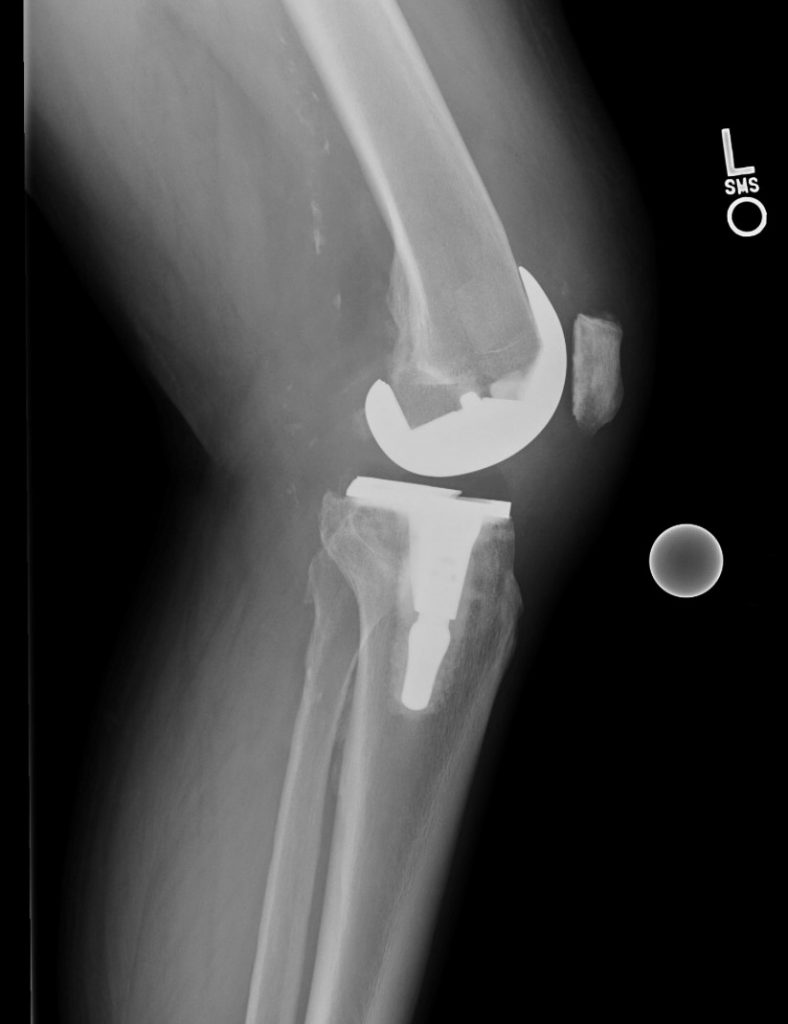

Knee Replacement

In 2 consecutive years I had both my knees replaced by Dr Elizabeth Gausden and as expected, there was considerable pain involved. After all, it is major surgery. But with the experience, professionalism and care of the surgical team and after-care support staff nurses, medical assistants and physical therapists, I am both happy and grateful that I chose HSS. I would not hesitate to tell anyone who asks that I recommend HSS as the best orthopedic hospital there is. To quote Dr Gausden, I now have a ‘matching set’.